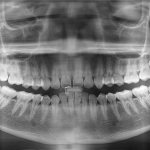

1. Диагностика. Этот этап включает в себя осмотр ортодонта, ортопантомограмму, то есть, создание круговой проекции ряда.

В процессе обследований задействуют рентгенологические снимки, с помощью которых ортодонт решает, какие именно единицы создадут значительное препятствие при коррекции прикуса.